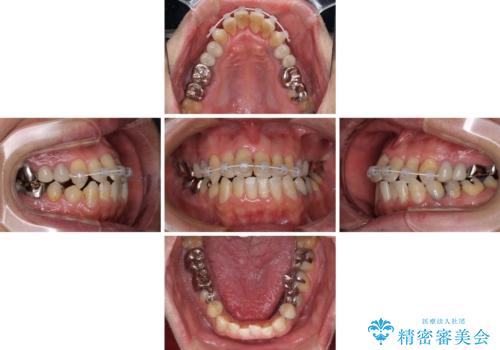

マウスピースで矯正を行いたい反面、一旦早めに前歯を整えたいというご希望があったため、まずは上顎前歯をワイヤー装置で整え、その後インビザラインにて仕上げていくこととしました。

ワイヤー矯正を併用したことで、上顎前歯はあっという間に整いました。

補綴治療中に前歯のデコボコが戻ってしまったため、補綴治療後にインビザラインを1セット追加して仕上げました。